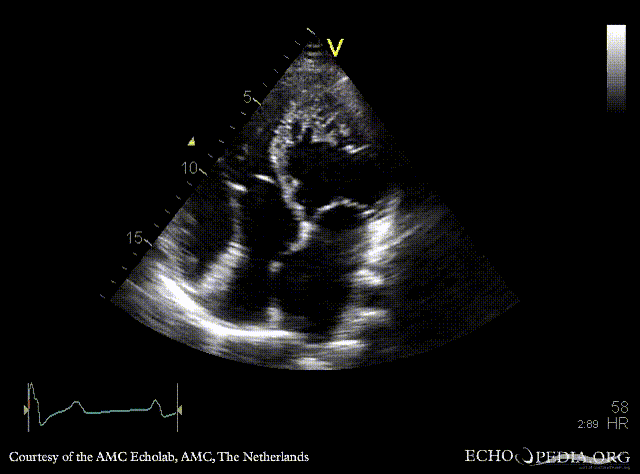

Ebstein anomaly and non-compaction cardiomyopathy

A4CH: high insertion of tricuspid valve, dilated right atrium and right ventricle, non-compaction of left ventricle A4CH with Color Doppler: severe tricuspid regurgitation